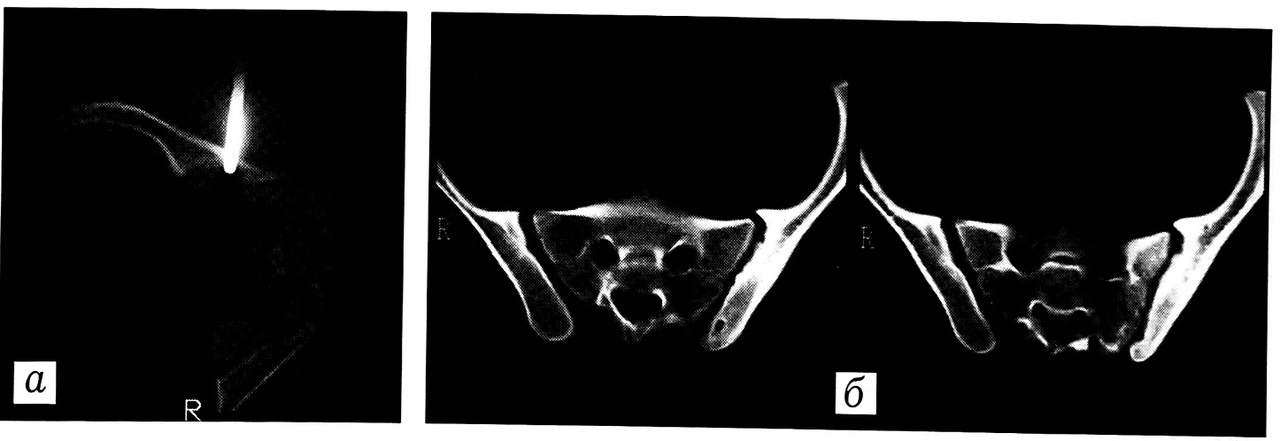

Рис. 5. Больной Б. Остеоидная остеома правой таранной кости. a — предоперационная разметка «гнезда» опухоли; б — контрольное обследование через 1,5 мес после операции

Предоперационная разметка под контролем КТ произведена в 14 случаях (в 12 — у детей и подростков), в том числе в одном случае — с извлечением винта из заднего края вертлужной впадины, в двух — с введением контрастного вещества в патологический очаг. У 9 пациентов при диагнозе остеоидной остеомы на основе навигации «якоря» в патологический очаг выполнена минимальная резекция (рис. 5). Во всех 9 случаях диагноз остеоидной остеомы верифицирован морфологически. В катамнезе клинико-рентгенологических признаков рецидива не выявлено.